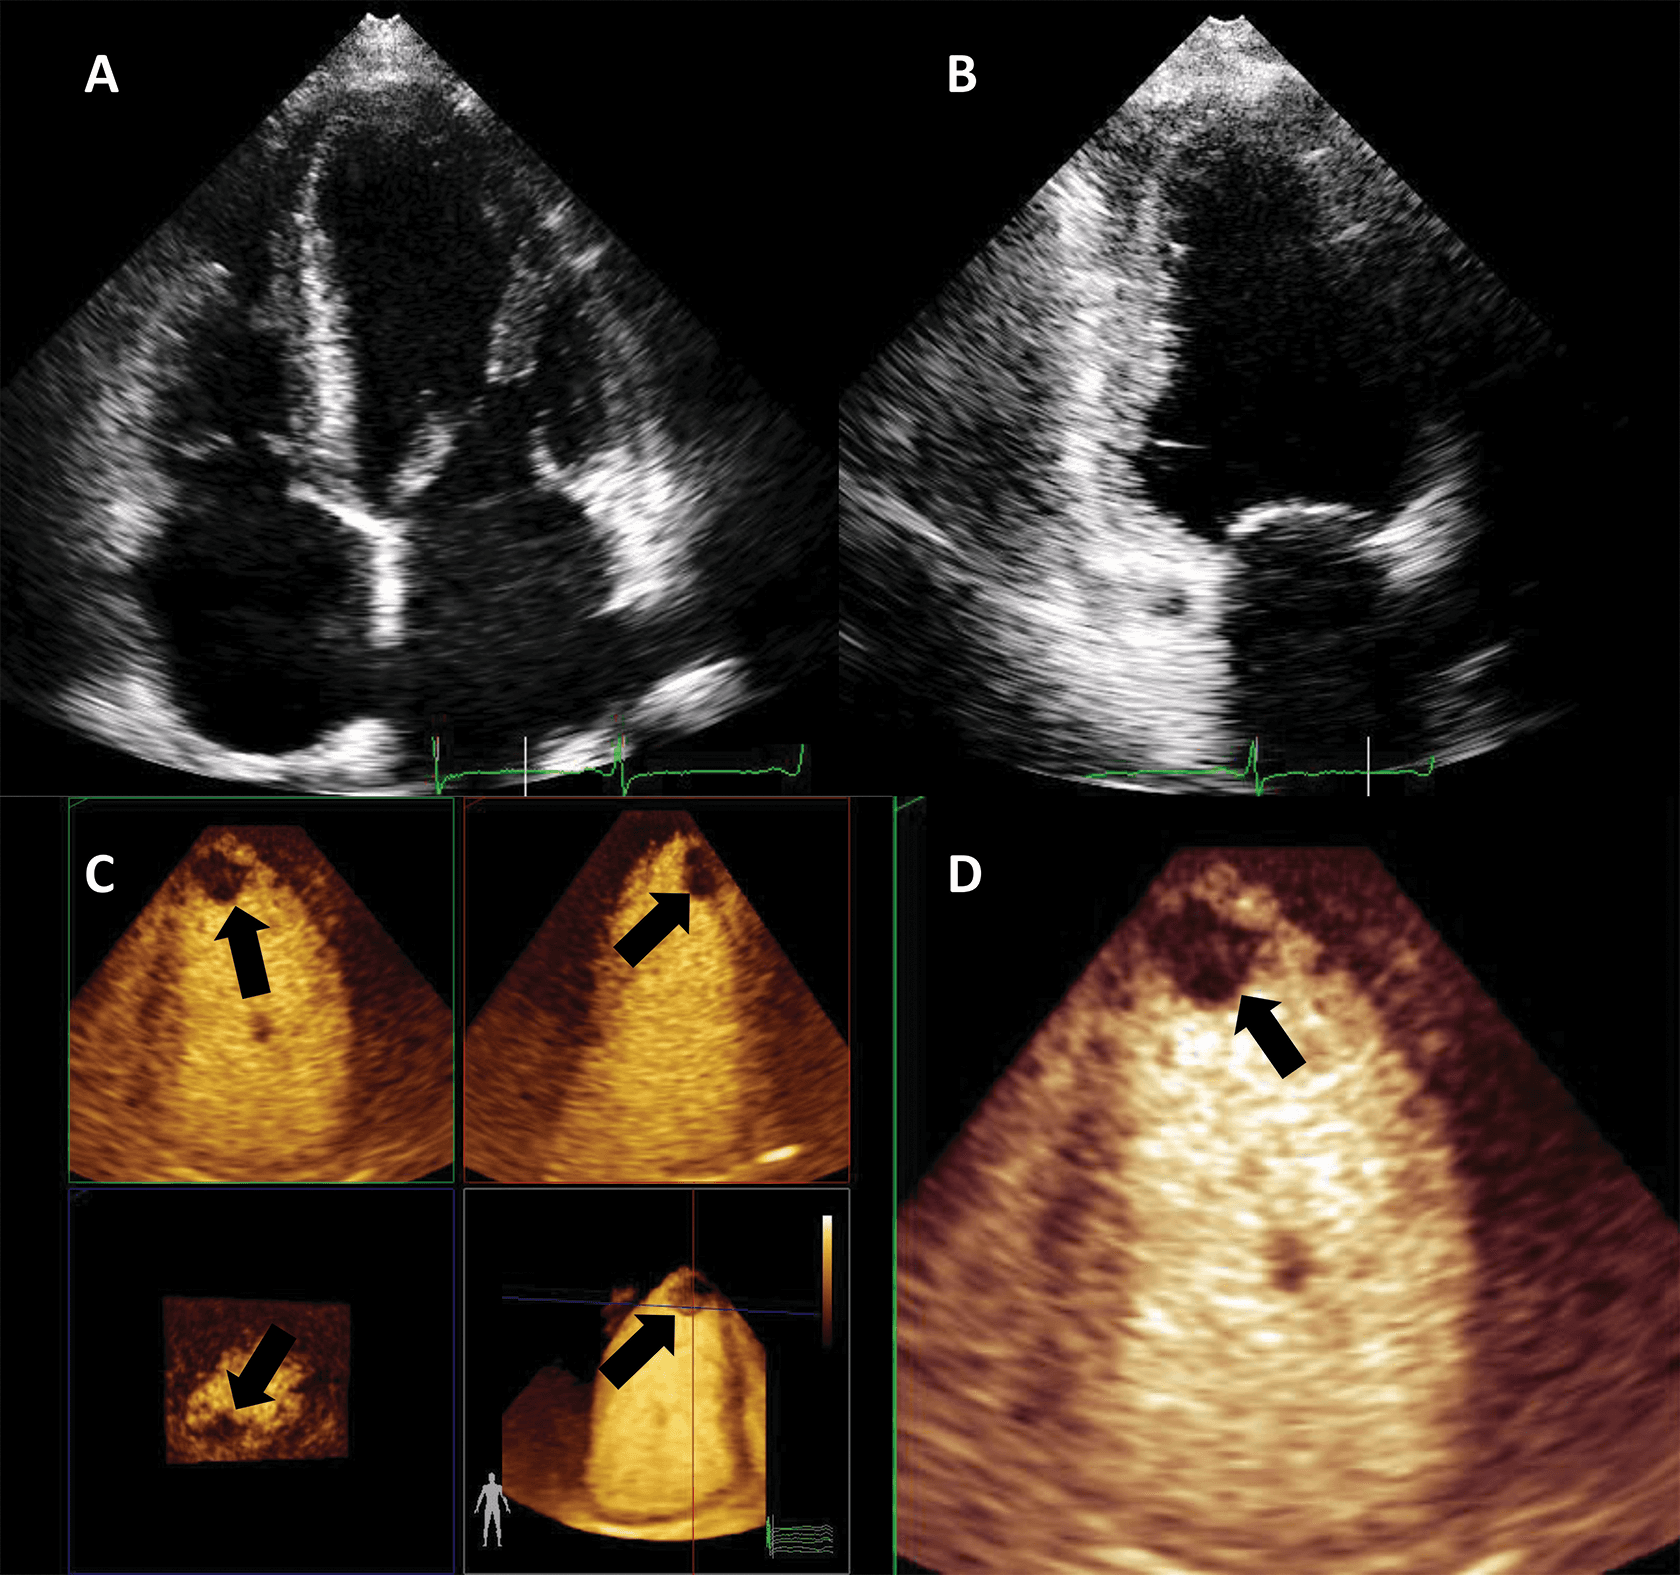

Another application of LVO is morphological diagnosis, particularly in disease states which manifest in the artefact-prone LV apex. Beside possible foreshortening, the LV apex is prone to clutter and reverberation artefacts, while also having a weaker potential to generate harmonics because of its position in the near-field in apical views [28]. As such, apical forms of hypertrophic cardiomyopathy [29, 30], eosinophilic cardiomyopathy [31] and non-compaction cardiomyopathy [32] may escape detection with unenhanced ultrasound.

Numerous case reports and case series document the use of UEA in these instances [29, 30, 31, 32, 33]. Studies have also been performed demonstrating the added value of contrast-enhanced ultrasound in hypertrophic cardiomyopathy [34] (Fig. 4, Video 4).

Fig. 4.Hypertrophic cardiomyopathy patient with very poor image in apical 4-chambers view. (A,B) Native images, end-diastole (A) and end-systole (B). The endocardium of the lateral wall is not visible, and the apex cannot be seen. (C,D) Contrast-enhanced images, in the same moments in the cardiac cycle. The LV contour is clearly delineated, during systole there is complete cavity obliteration, with an apical aneurysm (arrow). Source: personal collection.